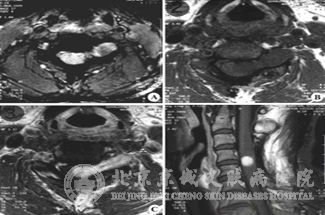

神经纤维瘤的瘤体一般情况下常位于上睑,而且质地比较柔软。但是由于瘤体的原因会使眼睑肿胀增厚,并伴有色素沉着,眼睑下垂的现象。如果用手去触摸,会触及到索状物质及小结节,但是并不会由于手的按压感到疼痛。

如果突发此病,一般情况下,常会伴有青光眼、虹膜、睫状体及脉络神经纤维瘤。此时会由于神经纤维瘤的原因引起眶骨缺损,从而可导致搏动性眼球突出或凹陷,并且与桡动脉一致。如果肿瘤原发于肌锥内,除了会有眼球突出的症状外,还会出现视力障碍的症状。